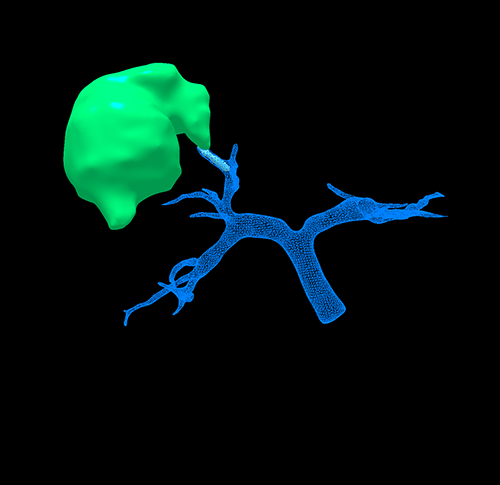

右肝肿瘤----腹腔镜右半肝切除